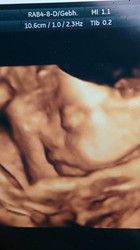

hab bissel angst bin jetzt in der 32 ssw lg